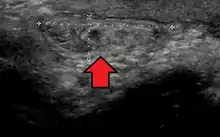

Ultrasound showing an inguinal hernia

By far the most common hernias (up to 75% of all abdominal hernias) are inguinal hernias, which are further divided into the more common indirect inguinal hernia (2/3, depicted here), in which the inguinal canal is entered via a congenital weakness at its entrance (the internal inguinal ring), and the direct inguinal hernia type (1/3), where the hernia contents push through a weak spot in the back wall of the inguinal canal. An indirect inguinal hernia and a direct inguinal hernia can be distinguished by their positioning in relation to the inferior epigastric vessels. An indirect hernia is situated laterally to these vessels, whereas a direct hernia is positioned medially to them. Inguinal hernias are the most common type of hernia in both men and women. In some selected cases, they may require surgery.